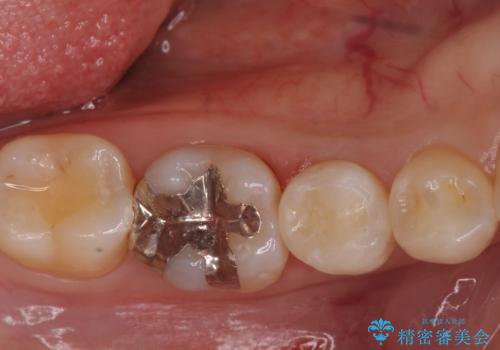

銀の詰め物を外し、拡大鏡で虫歯がないか確認してe-maxインレーで治療をしました。

- e-maxインレー 7.7万円 費用は治療当時の料金となります

白い詰め物が入り、大変満足して頂けました。

もう一つの歯も今後治療をしていきたいそうです。